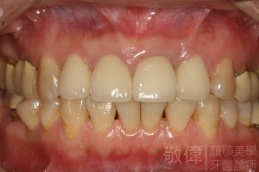

治療後上顎   治療後正面   治療後下顎

治療前-缺上排前牙   治療後